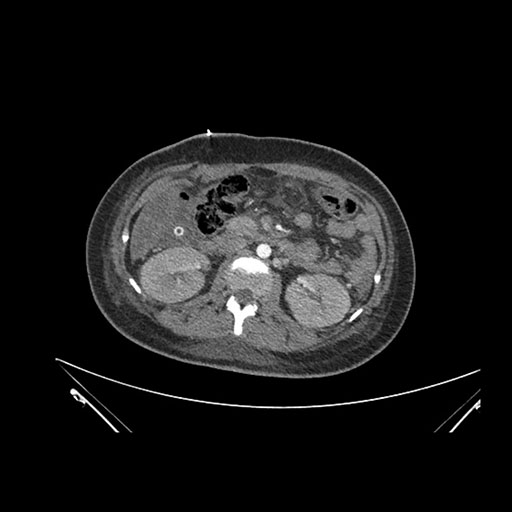

Axial Arterial